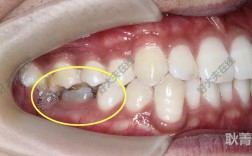

适用病例:因个别牙齿伸长导致深覆合、开合,或种植修复前需调整邻牙高度以获得共同就位道。

操作方法:在伸长牙齿的根方牙槽骨植入种植体,橡皮链以垂直向角度连接种植体与伸长牙齿托槽,施加持续压低力(约100-150g),种植体支抗提供垂直向稳定支抗,避免牙齿压低时邻牙倾斜,同时减少牙根吸收风险。